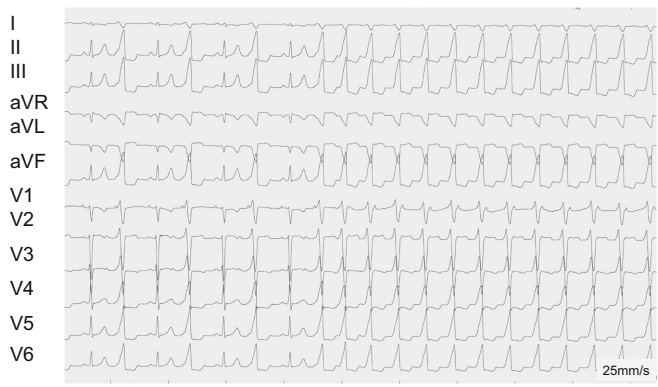

患儿以眼睑水肿和肝肿大起病,超声显示左心室舒张末径达57mm(Z值>4),LV-EF仅16%。心电图显示持续性RVOT VT(130-140bpm),呈左束支传导阻滞(LBBB)伴下壁导联高R波。